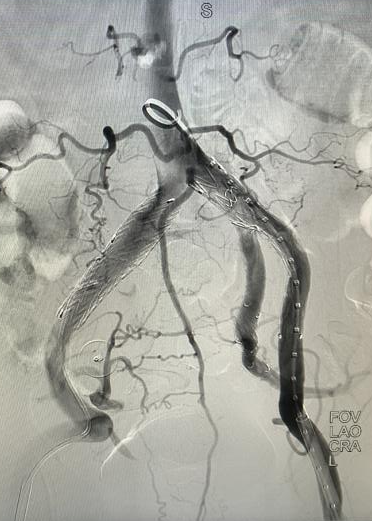

心脏问题解决后,治疗的“接力棒”交到了血管外科团队手中。团队预先在腹主动脉支架上为副肾动脉开窗并标记,随后在术中精准定位,将导丝导管通过开窗口超选入副肾动脉并成功植入支架,最终造影显示,腹主动脉瘤被完全隔绝,副肾动脉血流通畅,且无内漏。术后,患者肾功能维持良好,平安出院。

患者术前(左)、术后(右)DSA检查结果对比